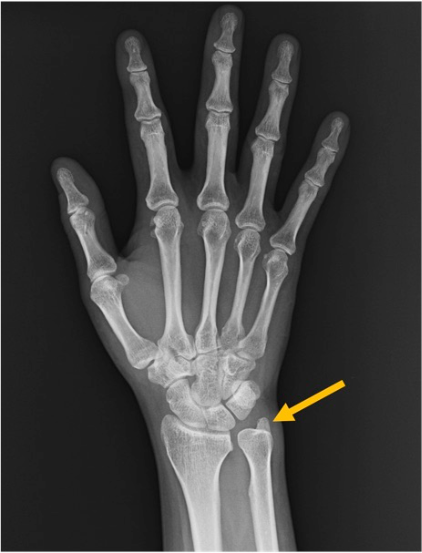

尺骨領域

尺骨茎状突起(ulnar styloid process)

尺骨遠位端背側〜尺側に突出。PAや側面像で茎状突起の位置と骨片(尺骨茎状突起骨折)を確認。TFCC損傷の臨床背景と併せて評価することがあります。

尺骨(ulna)

前腕の尺側骨。手関節X線では遠位部のみ視認。PAで橈尺関節(DRUJ)の整合、側面で重なり具合や背側/掌側転位の示唆を確認。

橈骨領域

橈骨(radius)

前腕の橈側骨。手関節X線では遠位橈骨(distal radius)が主要評価部位です。PA像では舟状骨窩(scaphoid fossa)と月状骨窩(lunate fossa)の連続性、DRUJ(遠位橈尺関節)の整合を確認。側面像では掌側傾斜(volar tilt)や背側転位、関節面段差(step-off)の有無をチェックします。